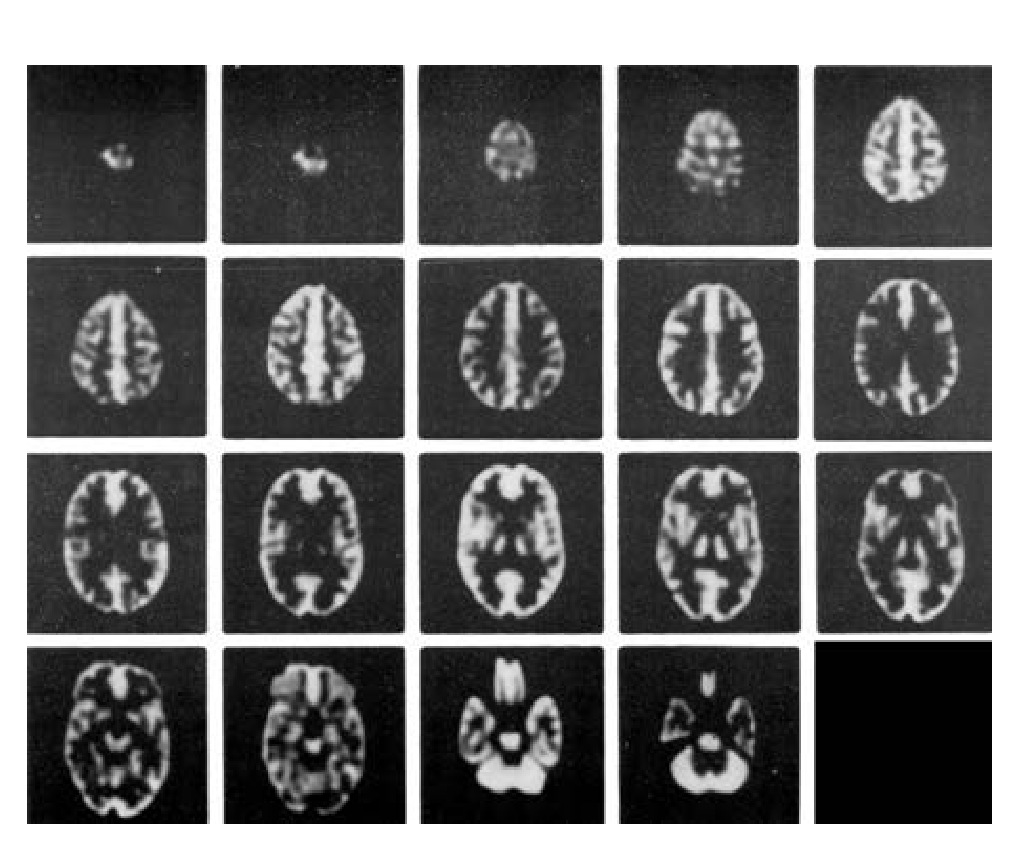

在腦部SPECT及腦部PET的研究中,從解剖學(xué)角度精確的模擬放射性分布;

在MRI研究中,精確模擬質(zhì)子密度及馳豫參數(shù)的分布。

● 在血流和代謝研究中模擬正常灰質(zhì)和白質(zhì)的 4:1 攝取率(按部分體積效應(yīng)模擬)。

可用于腦部ECT研究中對(duì)圖像獲取及重建方法的評(píng)估

3D重建方法評(píng)估

3D衰減及散射補(bǔ)償方法評(píng)估

3D,SPECT,PET及MRI系統(tǒng)配準(zhǔn)技術(shù)評(píng)估